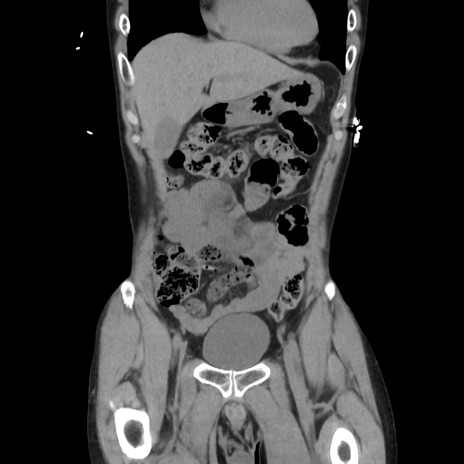

症例37(冠状断像)

【症例】40歳代 男性

【主訴】腹痛

【現病歴】4時間ほど前に電車に乗車中に臍部上より腹痛出現。徐々に増悪し起立困難となり、救急外来受診。生ものは数日食べていない。今朝お雑煮を食べた。

【身体所見】BT 36.8℃、BP 117/84mmHg、HR 91/min、SpO2 97%、苦悶様、腹部:臍上部広範囲圧痛あり、反跳痛±

【データ】WBC 8100、CRP 0.03